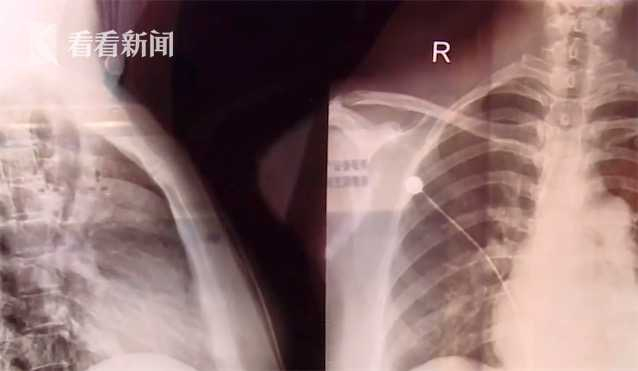

女子吃十年减肥药副作用频发 属心血管“癌症” 入院时已到“晚期”

专家介绍,肺动脉高压是一种凶险且恶性的心肺血管疾病,发病率在20岁到40岁之间,女性患者比例高。

该病隐蔽性大,初期症状比较轻微,主要病症为胸闷气促,所以容易遭到患者的忽视。如不干预治疗,生存时间不到3年。